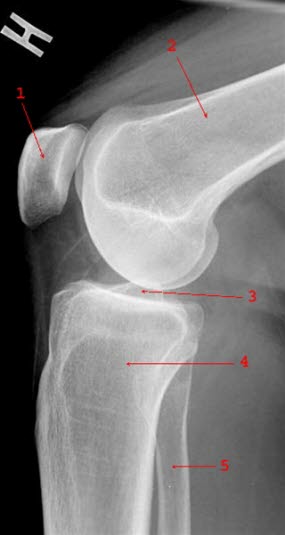

Se røntgenbilde av kneleddet forfra og fra siden.